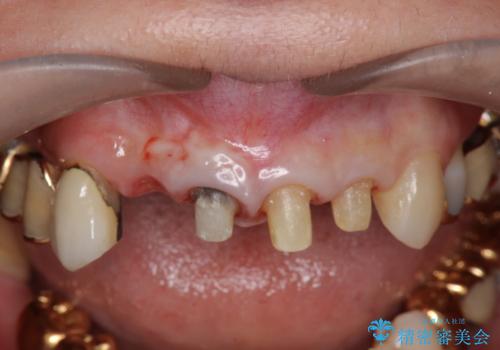

再根管治療を行うべくクラウン除去を行ったところ、右上側切歯に保存不可能な垂直性の破折が認められたため抜去が必要になりました。

即切歯の抜歯を行う場合犬歯を含めたブリッジによる補綴計画を立てることが多いですが、今回は犬歯から大臼歯にかかる大きなブリッジが既に装着されていたため予算とご希望を相談し前歯のみの延長ブリッジ補綴で治療を行っていくこととしました。